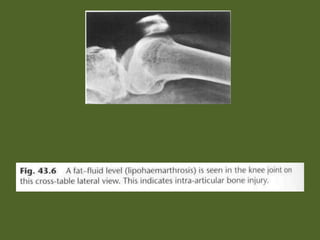

43 DAVID SUTTON PICTURES SKELETAL TRAUMA : GENERAL CONSIDERATION